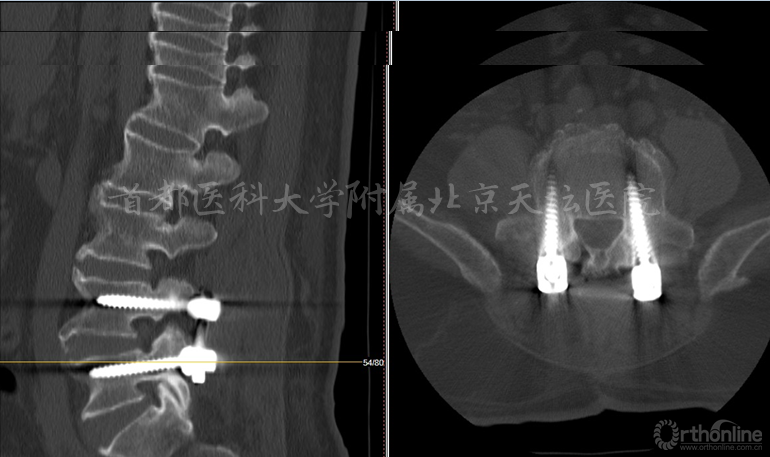

主诉:腰椎术后6年,腰痛1年,进行性加重伴双下肢麻木无力8个月

现病史:患者6年前出现腰痛伴右下肢放射痛,麻木及无力,于外院行棘突间内固定装置(Wallis)手术,术后症状部分缓解,未复查。1年前患者再次出现腰痛及下肢放射痛,8个月来呈进行性加重,现疼痛剧烈,不能久坐,不能站立及行走,平卧位不能缓解,服用止痛药物效果不佳。

影像资料:

诊断:

• 腰椎管狭窄症(双侧神经根管狭窄)

• 棘突间植入物术后(Wallis)

• 棘突骨折

针对此病例,各位专家的讨论焦点主要落在棘突间植入物的疗效究竟如何上。天坛医院刘宝戈教授针对这个病例指出,患者曾在外院行棘突间植入物手术,术后不久再次出现症状,翻修手术如何进行?这需要细致的考量。针对该例老年患者,他们最终选择了微创的治疗方式,基于术前精确责任节段的定位,术后疗效满意。